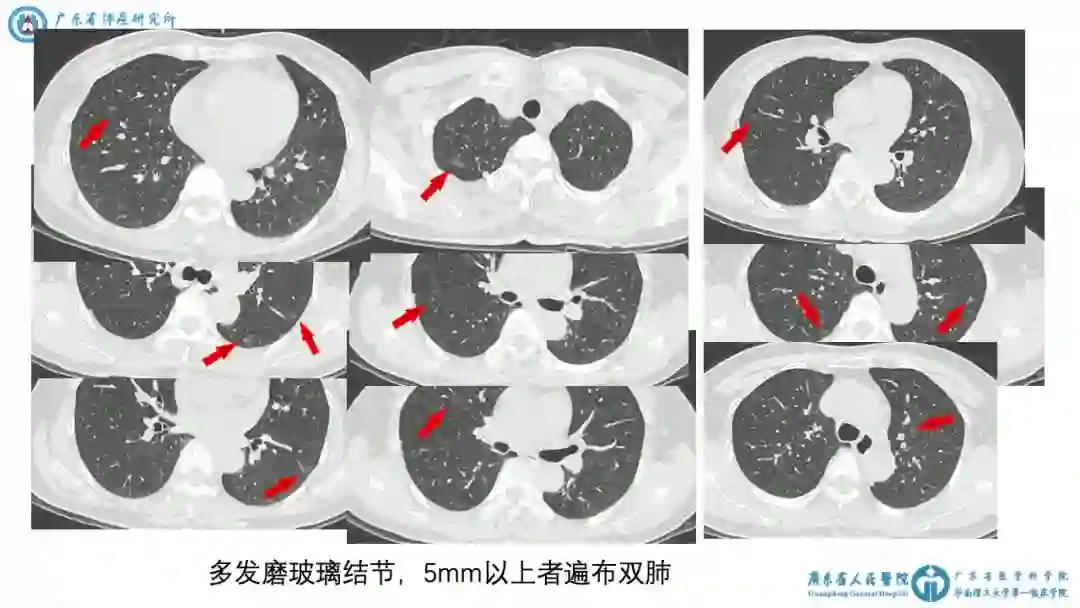

2)2018-10-16 胸CT平扫+增强:①左肺上叶斑片影,考虑慢性炎症。②多发磨玻璃结节,最大者左下肺8mm。③多发磨玻璃结节,5mm以上者遍布双肺。